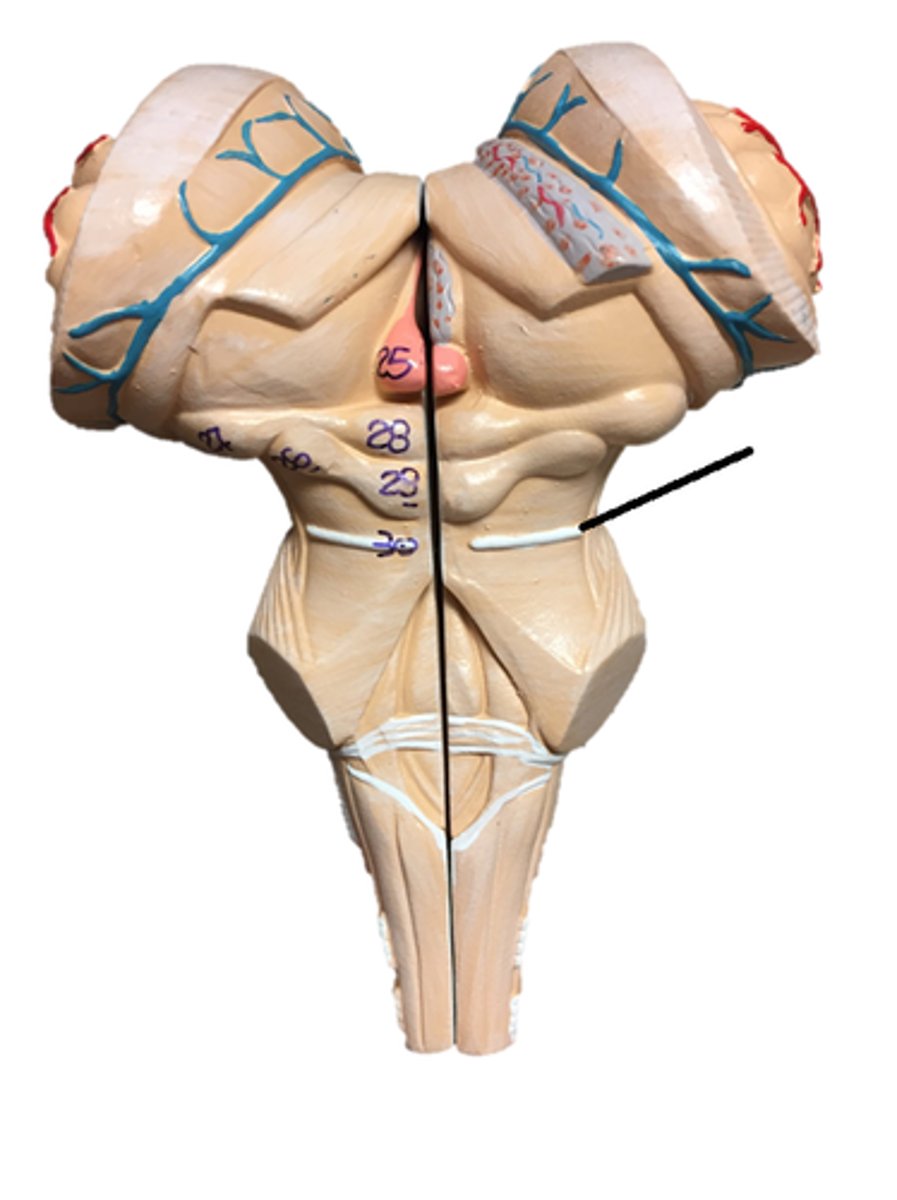

Cerebellum

anterior lobe of cerebellum

posterior lobe of cerebellum

vermis

cerebellar peduncles

folia

pons

midbrain

medulla oblongata

olive

superior colliculi

inferior colliculi

cerebral peduncles

arbor vitae

Primary fissure